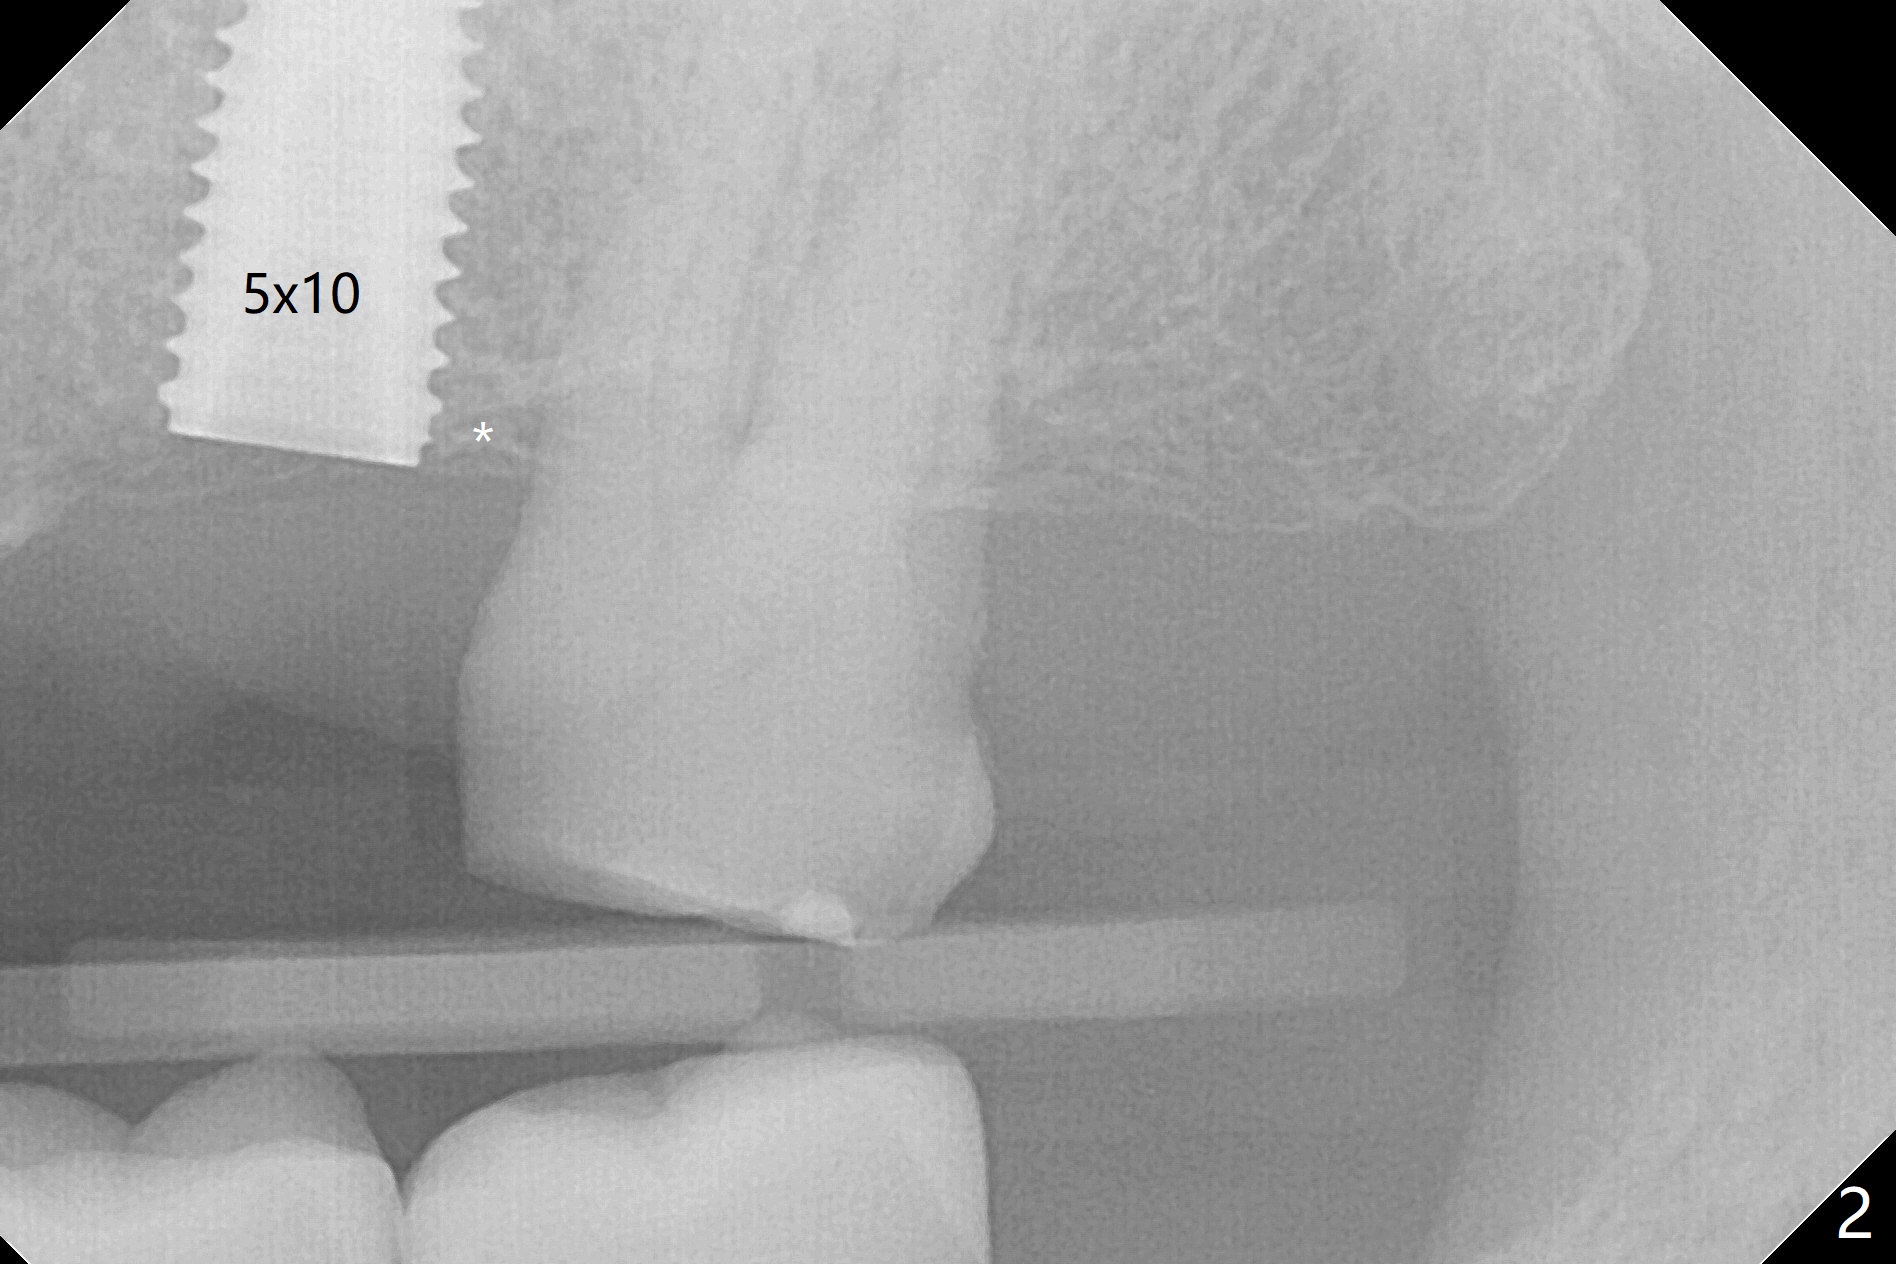

After extraction of the tooth #13 residual root, the bone in the distal wall of the socket looks white. Intraop PA rules out root structure (Fig.1 *). Osteotomy is conducted according to drill sequence. Bitewings are taken to check implant placement level (Fig.2,3). Following implant level adjustment and healing abutment installment (Fig.4,5 (*: bone graft)), the implant at #13 is found to be close the root of #12 (Fig.6 *), i.e., not parallel to the implant at #14. Introspectively, 2.2x10 mm drill seems to be long. When it touches the bone, the cylinder portion of the drill (Fig.7 red) does not engage into the sleeve (green). When it goes into the bone, it may have been deflected mesial due to the slope of the distal wall of the socket (hard bone, Fig.8 open arrow)). If a shorter drill (such as 2.2x7.3 or 8.5 mm) were used (Fig.9), the deflection would be minimal if drilling is slow (Fig.10). CT taken 1 week postop shows that the implant at #13 is approximately 1 mm near the root of the tooth #12, but the neurovascular bundle to the latter seems not to have been interrupted (Fig.11,12). The buccopalatal trajectory at #14 is within normal limit (Fig.11,13 (B: buccal)). There is no periapical radiolucency at #12 five months postop (Fig.14). However the cemented abutments are incompletely seated (<). The patient is reluctant to return for impression 17 months postop (due to coronavirus); with attention, the same abutment at #13 is reseated completely; an abutment with longer cuff and narrower diameter is also seated completely (Fig.15).